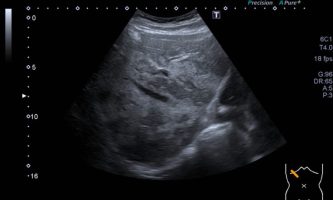

El médico de referencia le indica nueva ecografía de control, donde se observan múltiples y extensas lesiones focales hepáticas hiperecogénicas, redondeadas y confluentes, las cuales predominan en adyacencia a venas supra hepáticas, sin condicionar efecto de masa y sin alteración de la superficie hepática(fig. 1 y 2). Ante la valoración con Doppler color no presenta patrón de flujo peri ni intralesional y respeta el calibre de las venas supra hepáticas(fig. 3 y 4). Dada las características ecográficas se sospecha esteatosis focal multinodular confluente como principal diagnóstico presuntivo, siendo los diagnósticos diferenciales patologías de naturaleza infecciosa, tumoral o metastásica.